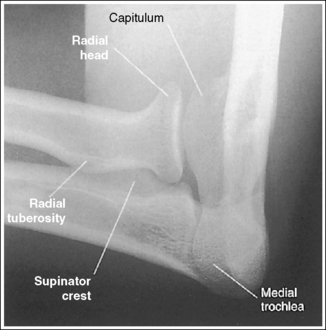

The capitulum and medial trochlea are demonstrated without superimposition, and the radial head is superimposed on only the anterior tip of the coronoid process.

• The axiolateral elbow projection is obtained by placing the patient's elbow in a lateral projection, with the humeral epicondyles aligned perpendicular to the IR and placing a 45-degree proximal (toward the shoulder) angle on the central ray (Figure 4-85). It is this humerus and central ray positioning that accurately separates the capitulum and trochlea of the distal humerus and positions the radial head anteriorly to the coronoid process. The combination of positioning and angulation projects the anatomic structures (radial head and capitulum) situated farther from the IR proximal to those structures (coronoid process and medial trochlea) situated closer to the IR.

• Effects of errors in positioning or angulation. If the central ray is angled accurately but the proximal humerus is depressed lower than the distal humerus, the medial trochlea and capitulum cortices are not clearly defined, the coronoid process is free of radial head superimposition, and the radial neck and tuberosity are superimposed by the ulnar supinator crest (a sharp, prominent ridge running along the lateral margin of the ulna that divides the ulna's anterior and posterior surfaces; see Image 97). The same image can result if the patient is accurately positioned but the central ray is angled more than 45 degrees.

The capitulum-radial joint is open, and the proximal radial head and coronoid process are aligned.

• An accurately aligned radial head and coronoid process and an open capitulum-radial head joint is obtained when the elbow is in a lateral projection. A lateral elbow projection is accomplished when the humeral epicondyles are positioned directly on top of each other, placing them perpendicular to the IR (see Figure 4-85).

The radial head surface of interest is demonstrated in profile.

• The position of the wrist determines which surface of the radial head is placed in profile.

• Effect of wrist position. When the patient's elbow is placed in a lateral projection, wrist rotation causes the radius to rotate around the ulna. This rotation places different radial head surfaces in profile. To determine which surfaces are in profile, one should become familiar with the relationship between the wrist position and visualization of the radial tuberosity. The radial tuberosity is adjacent to the medial aspect of the radius. If the tuberosity is demonstrated, the medial aspect of the radial head is also shown on that same surface and the lateral aspect of the radial head is visible on the opposite surface. If the patient's wrist is positioned in a PA projection, the radial tuberosity and medial radial head are demonstrated posteriorly and the lateral radial head appears in profile anteriorly (see Image 98). If the wrist is in a lateral projection, the radial tuberosity is not demonstrated in profile but is superimposed by the radius. In this position, the anterior radial head is demonstrated in profile anteriorly and the posterior surface is shown in profile posteriorly (see Image 93).